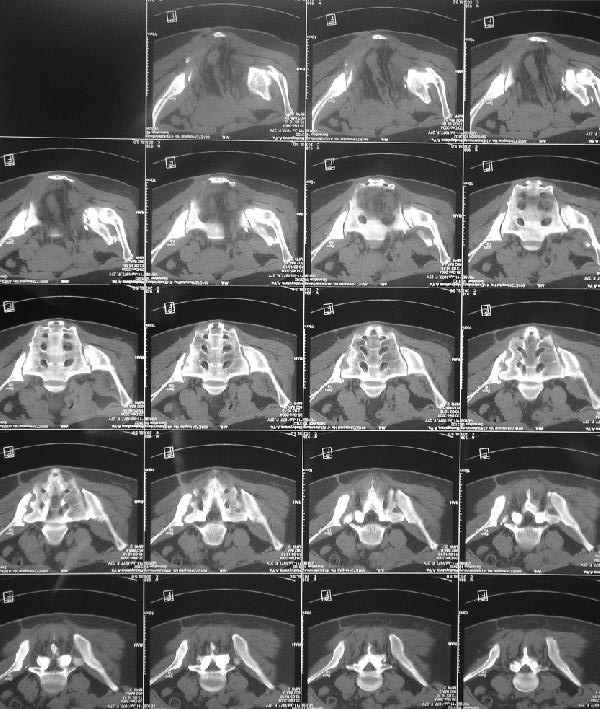

По просьбам коллег отправляем снимки таза: прямая, inlet, outlet, 2 дополнительные компьютерные томограммы.

Should you deem her fit for surgery, the 3-D CT alone is insufficient for planning preoperatively. We can¹t see the healing response, soft tissue envelope, the right SI injury, nor the left SI joint problem well enough on the 3-D CT alone.

In other hand, I would like to see the primary X rays, because with 3D-CT alone I cannot classify that fracture into Letournel's classification. Maybe it is a posterior hemitransverse with anterior column fracture.

О виртуозности владения аппаратным лечением, неоднократно доказанным на ваших материалах, со стороны русских коллег, все таки голосую за многоэтапность лечения, конечно после нормального обследования, снимки таза: прямой, инлет, оутлет и КТ, а представленная 3D, не представляю

во сколько обошлась больной, кроме красивого рисунка, не дает нужную информацию для специалиста. Обычные КТ срезы дают информацию о

сращении, от которого и зависит тактика лечения.